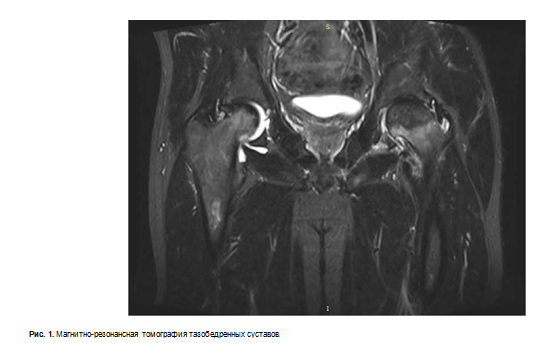

Через сутки после оперативного лечения выполнен рентген правого тазобедренного сустава (рис. 2). Состояние всех компонентов эндопротеза удовлетворительное.

Пациент выписан из стационара на 8 сутки после оперативного лечения в удовлетворительном состоянии для продолжения реабилитации по месту жительства. Рекомендовано динамическое наблюдение кардиолога и травматолога ГБУЗ "НИИ — ККБ1". Продолжить антикоагулянтную терапию препаратом ривароксабан 10 мг/сут. в течение 5 нед., иммуносупрессивную терапию в прежнем режиме, под контролем концентрации такролимуса и эвероли- муса (метилпреднизолон отменен), гипотензивную терапию.